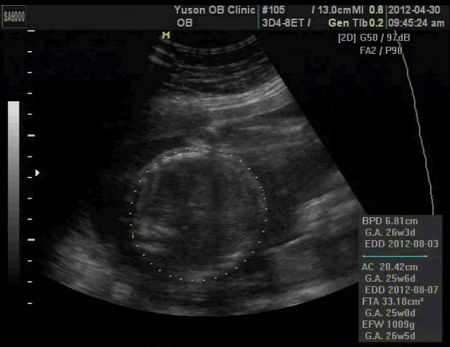

測量頭圍、肚圍估體重

醫生說26週寶寶正常體重是要1000克左右,我兒子剛好是1009克,醫生說他都有照進度在大喔!哈哈!